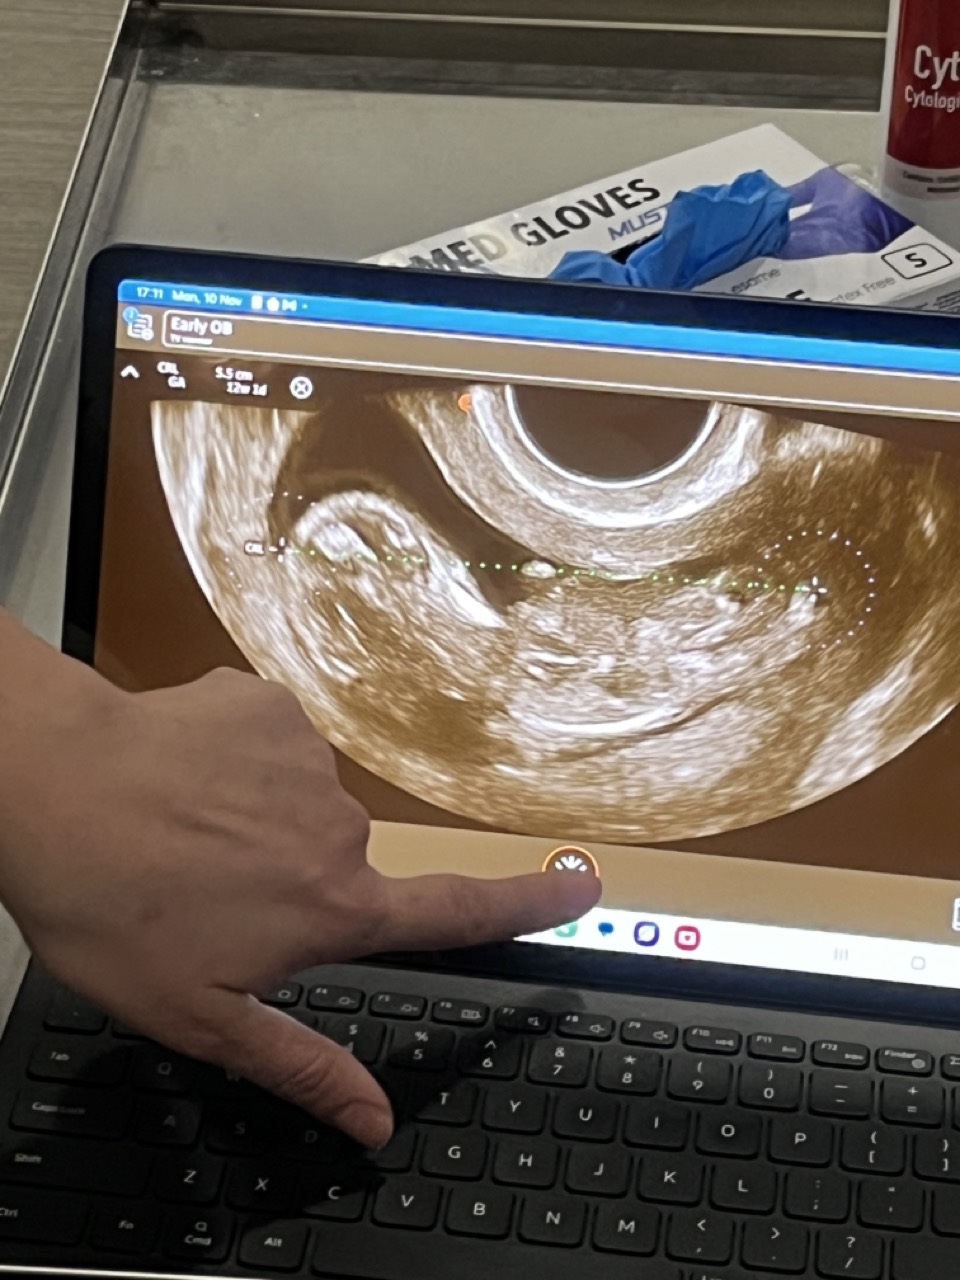

Yesterday we got to see our baby again (3rd time so far) on an ultrasound.

11 weeks, 4 days, and due in May 2026.

Tiny arms, legs, and head. Already moving around.

We think it might be a boy.

Saw something between the legs.

The doctor said it could be the cord, but still. We noticed.

Either way, everything looked good.

Heartbeat strong. Growth on track.